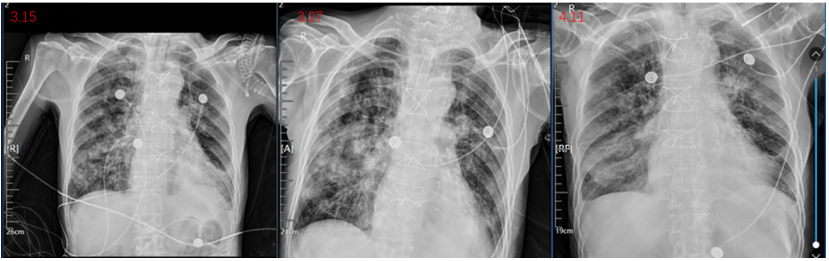

3月26日肺泡灌洗液tNGS提示铜绿假单胞菌(序列数7889)、嗜麦芽窄食单胞菌(序列数3972)、肺炎克雷伯杆菌(序列数63)、人疱疹病毒1型(序列数1127)(检出耐药基因KPC、CTX);血tNGS示铜绿假单胞菌(序列数10)、嗜麦芽窄食单胞菌(序列数95)、肺炎克雷伯杆菌(序列数33)、人疱疹病毒1型(序列数954)。痰培养提示嗜麦芽窄食单胞菌(复方新诺明、左氧氟沙星、米诺环素均耐药),改用头孢他啶阿维巴坦+氨曲南抗感染、更昔洛韦抗病毒。治疗过程中多次支气管镜检查及气道廓清,输注人血白蛋白纠正低蛋白血症、悬浮红细胞纠正贫血、血小板纠正血小板减少,同时抗心衰、升压、控制心率、营养支持、润肠通便及对症治疗。患者病情逐渐平稳,复查胸片可见肺部渗出逐渐吸收(图4)

图片

4  治疗过程中动态复查胸部平片